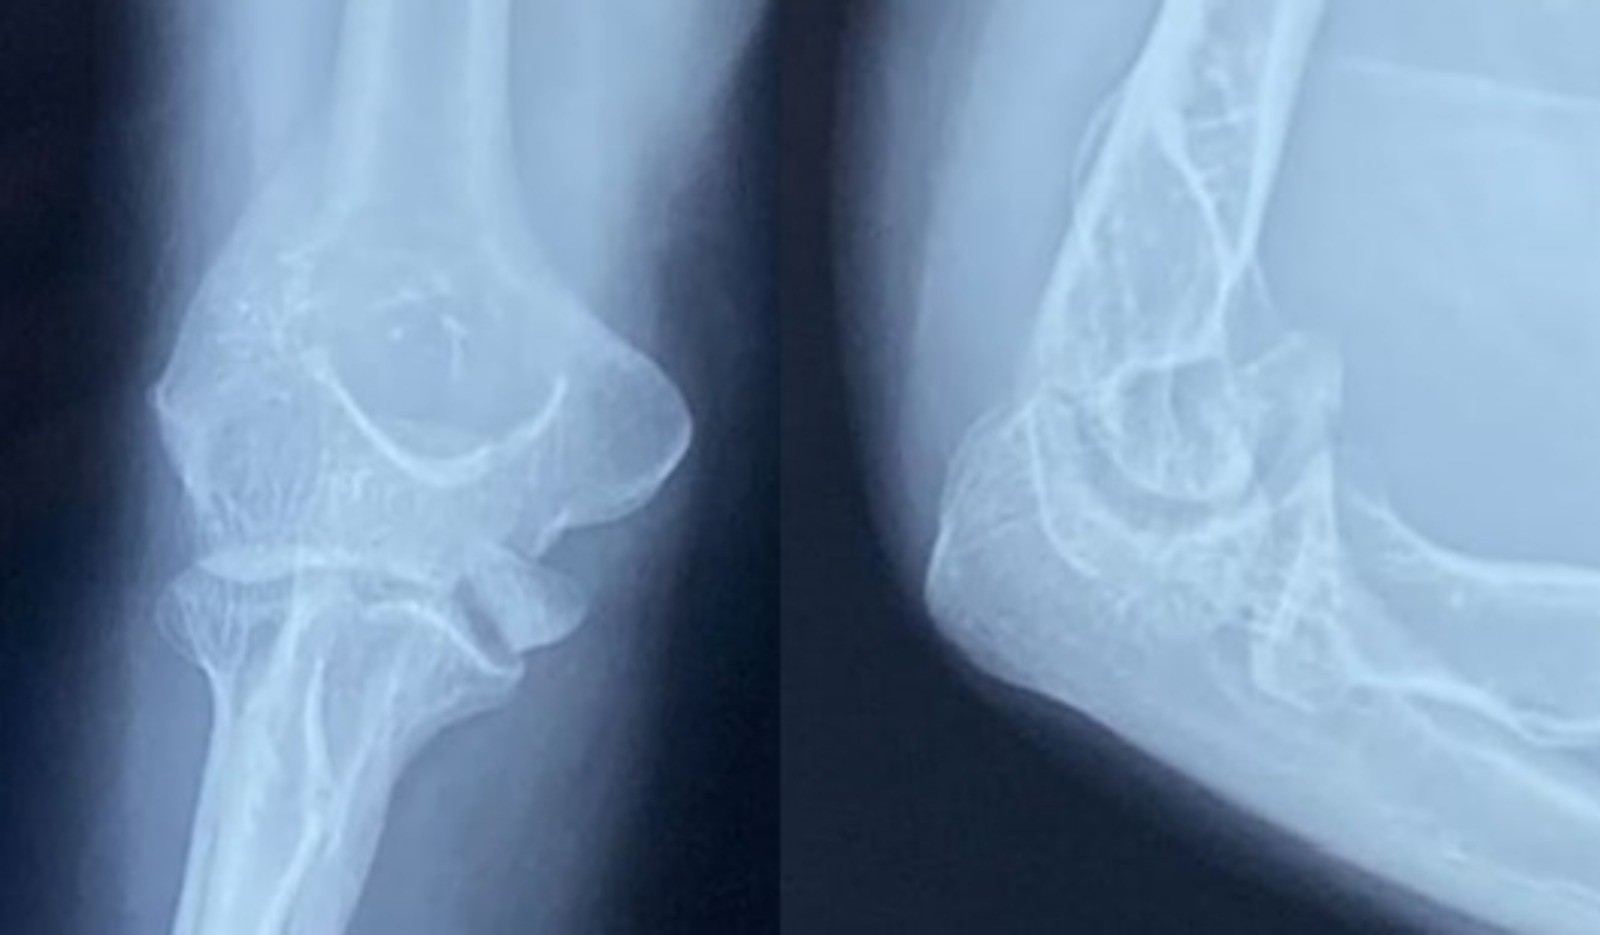

We present the case of a 35-year-old female who presented 3 weeks post-traumatic injury to her elbow. She had a fall on the flexed elbow with force directed through the olecranon tip proximally. She was initially managed with a splint in 90° elbow flexion and forearm supination. She was advised conservative management for the fracture, including immobilization for 8 weeks followed by gradual physical therapy; however, she presented to us due to constant pain and restricted elbow range. On examination, she exhibited swelling and tenderness over the medial elbow without wounds or distal neurovascular deficit. Plain radiographs of her elbow showed a half-moon-shaped fragment displaced anterosuperiorly with irregular ulnohumeral articulation in the lateral X-ray. No dislocation of the elbow joint or the radial head was noted. These findings were corroborated on subsequent computed tomography (CT) scans (Fig. 1 and 2).

Figure 1: Anteroposterior and lateral radiographs showing anterosuperiorly displaced trochlear fragments.